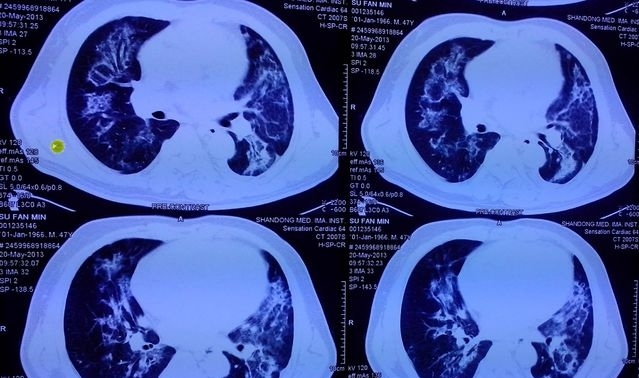

●在影像学上,尿毒症肺最典型的胸片则表现为“双侧肺野蝶翼状或蝙蝠状的渗出影”,说白了也就是以我们的肺门为中心,形成如蝶形或蝙蝠样阴影,如下图。我们大体上可将它的影像特点划分为5期,即肺泡性肺水肿期、肺淤血期、间质性肺水肿期、肺间质纤维化期和心脏扩大期。

尿毒症肺,影像中显著的渗出影

●但从个人经验来看,临床上还是以肺泡性水肿和心脏扩大期多见,因为这两种多会发生心衰,但这和普通的肺部感染是有着显著区别的,临床上如果能充分透析脱水这种蝶形或蝙蝠样渗出影可迅速消失,所以保证透析的充分性、增加超滤至关重要,也是这一并发症的核心治疗方案。